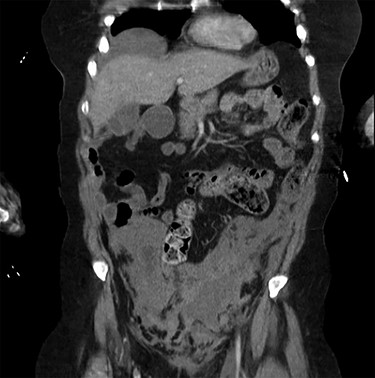

A 60-year-old Caucasian female was referred by her GP for a 2-day history of pain and swelling of the left leg. On examination, there was obvious limb swelling and a mass in the left iliac fossa. Soon after the presentation, the patient became hypotensive and arrested requiring cardiopulmonary resuscitation (CPR). The initial working diagnosis was PE secondary to DVT. Baseline investigations were normal but arterial blood gases showed compensated metabolic acidosis. After resuscitation, an urgent CT of abdomen, pelvis and chest was organized; this confirmed DVT of the left common iliac vein and also a large left adnexal mass with minimal ascites (Fig. 1). The patient, evidently in hypovolemic shock, was transferred for urgent exploratory laparotomy. She was found to have a large retroperitoneal haemorrhage with blood welling from the region of left iliac vessels. Proximal and distal control of iliac artery and vein was gained by tape and clamps allowing perioperative hypotension to improve. The vascular surgeon was called for help from the nearest tertiary centre. Upon further dissection, in the presence of the vascular surgeon, bleeding was noticed around the left common iliac vein, coming from the severed collaterals; these were eventually controlled with 6/0 prolene sutures. As the source of bleeding was not very clear, an opinion from vascular radiologist was sought. Review of the CT suggested that bleeding was likely to represent spontaneous rupture of venous collaterals due to DVT in the left iliac vein, secondary to MTS (Fig. 2). The patient was transferred to ITU with plans for relook surgery in next 48 hours once she had recovered from the acute insult. Unfortunately, the patient died the next day due to multi-organ failure and DIC secondary to massive transfusion.

Coronal view of the CT scan showing the localized pelvic haematoma.